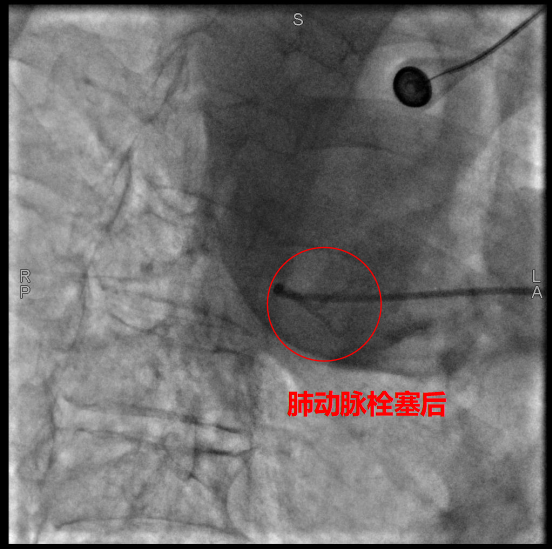

術(shù)中,數(shù)字減影血管造影(DSA)顯示患者右側(cè)支氣管動脈及胸廓內(nèi)動脈增粗紊亂,末梢血管可見造影劑點狀外溢,明確為主要出血責(zé)任血管。團(tuán)隊采用400?μm栓塞微球及560–710?μm明膠海綿顆粒,對出血動脈遠(yuǎn)端實施精準(zhǔn)栓塞,實現(xiàn)“末梢血管封堵”;同時,對肺動脈分支血栓相關(guān)區(qū)域也予以栓塞處理,以全面控制咯血來源。術(shù)后造影確認(rèn)出血完全停止,患者安返病房后未再咯血,胸悶、氣促等癥狀顯著緩解。